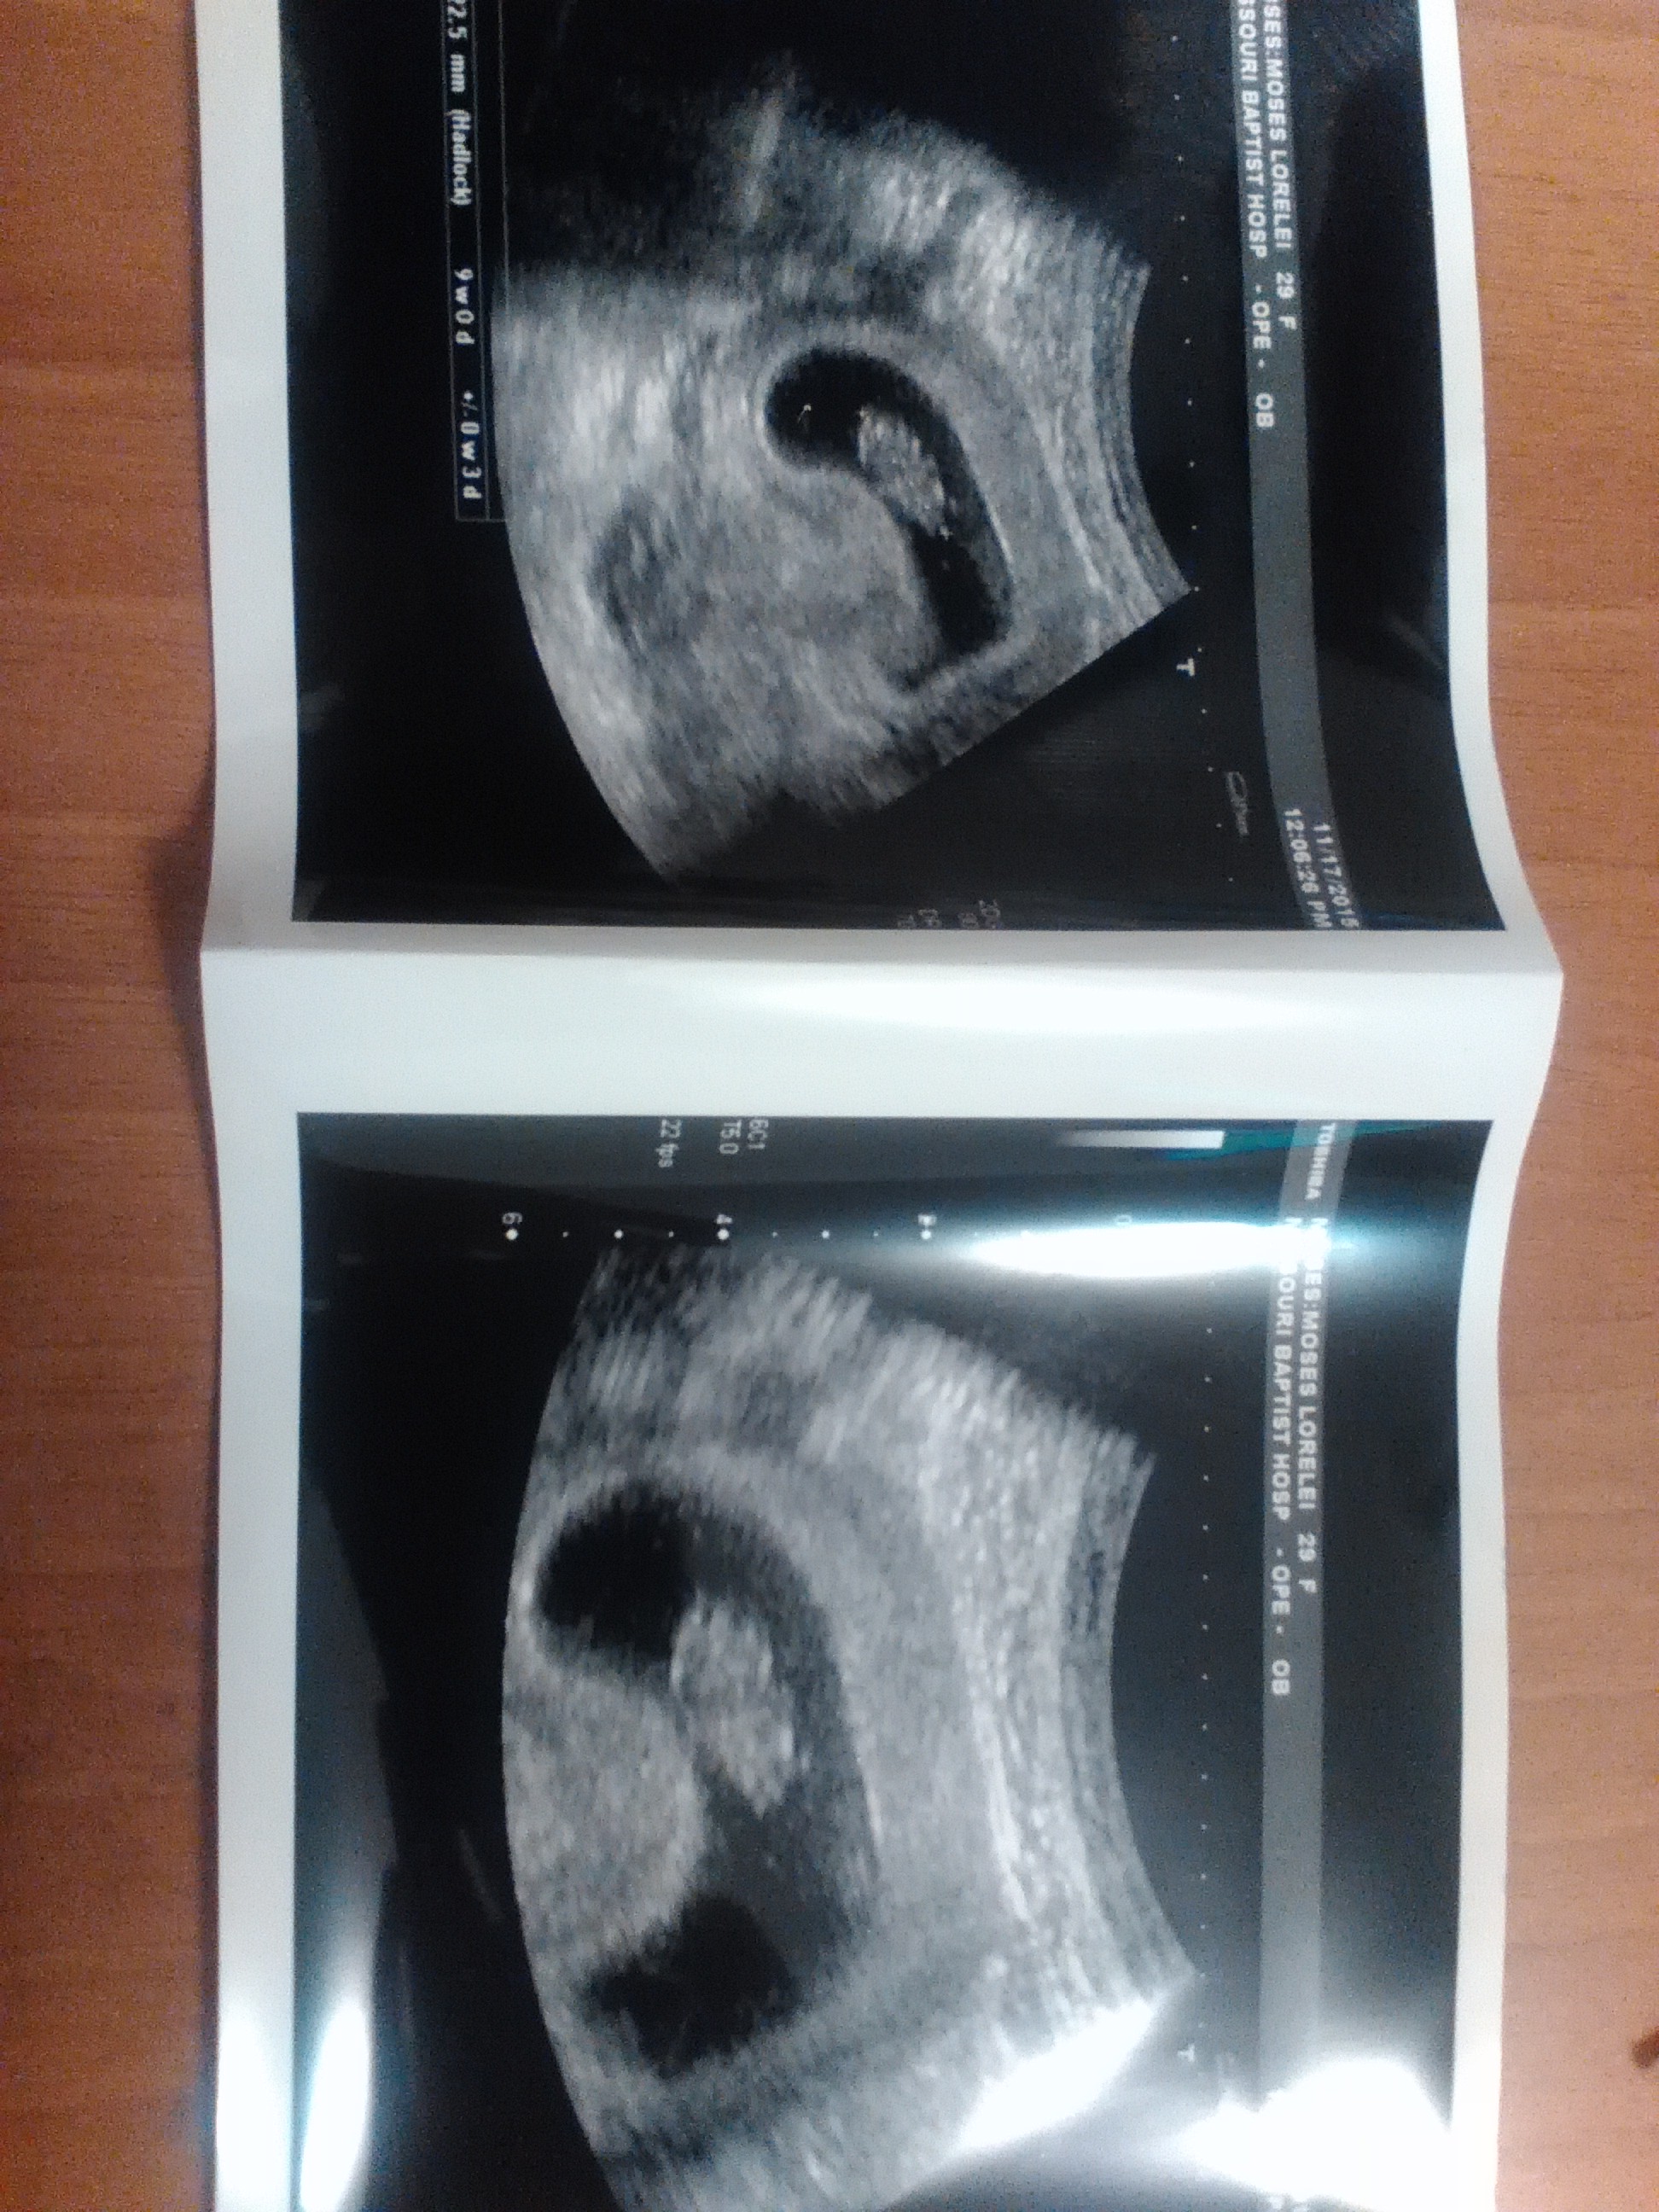

This was from my nine week appointment. Tomorrow I go for my 13 weeks and my doctor thinks he might be able to determine the gender. Isn't it a bit early for that though? I mean I really want to know but...